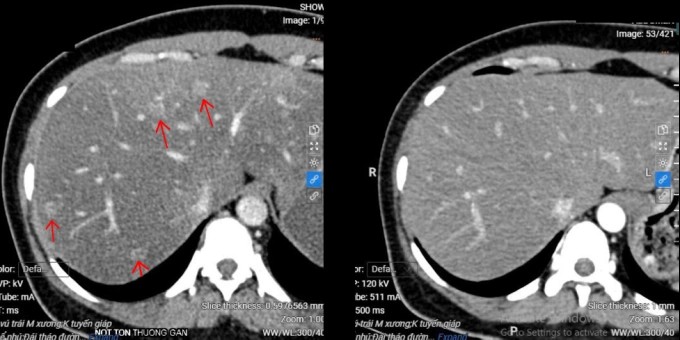

Sau ba năm, kiểm tra cho thấy khối u vú của chị Phương không còn, các nốt di căn gan tiêu biến, tổn thương xương đặc hóa, không gây đau. Suốt quá trình điều trị, chị không gặp tác dụng phụ đáng kể, không rụng tóc hay buồn nôn mà ăn uống ngon miệng, sinh hoạt bình thường. Hiện, chị Phương tiếp tục được tái khám định kỳ và điều trị duy trì.

Còn chị Nguyệt 38 tuổi, ung thư vú di căn gan, phổi năm 2023, xét nghiệm dương tính với thụ thể hormone và âm tính với protein HER2. Sau một năm điều trị bằng thuốc CDK 4/6, các nốt di căn gan, phổi thu nhỏ, sức khỏe người bệnh cải thiện hơn, không bị rụng tóc, thể trạng tốt. Hiện sau hai năm, tình trạng bệnh của chị vẫn được kiểm soát.